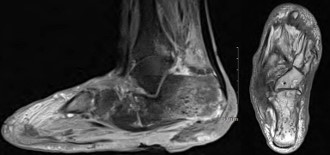

Left foot radiographs showed significant soft tissue defects and osteolysis within the inferior calcaneus, highly suspicious of underlying osteomyelitis (Figure 2). A Magnetic Resonance Imaging (MRI) of the left foot was ordered for further evaluation of underlying osteomyelitis. The result was concerning for osteomyelitis within the calcaneus with multiple punctate low signal foci suspicious of emphysematous osteomyelitis. The MRI also showed multiple fluid collections within the hindfoot and midfoot (Figure 3).

Figure 3: Sagittal T1 and axial T1 Fat-Suppressed magnetic resonance images that demonstrate the multiple punctate low signal foci of emphysematous osteomyelitis within the calcaneus.